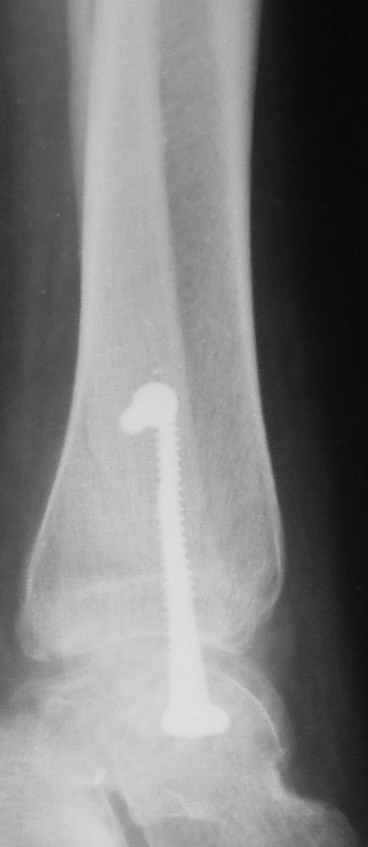

Ниже рентгенограммы

15 ноября прямой

15 ноября боковой

15 ноября трехчетвертной

12 января прямой

12 января боковой

12 января трехчетвертной

Риторический вопрос - в каком руководстве рекомендован такой способ остеосинтеза наружной лодыжки?

Очевидно, такой результат операции был запрограммирован. При невосстановленной длине и практически нефиксированной малоберцовой кости (этот кортикальный винт - как карандаш в стакане), при неустраненном подвывихе, невправленной и тоже нефиксированной внутренней лодыжке нет стабильной вилки сустава. Если такую операцию сделать даже сразу, а не через 4 месяца, то результат ожидаем

тот же.

Вообще говоря, такое повреждение вполне успешно можно лечить без операции - если 6 недель подержать в гипсовом "сапожке" с хорошо устраненным подвывихом. Вероятное несращение внутренней лодыжки не обязательно компрометирует результат.

Ну а уж если выбран остеосинтез - нначать надо было с репозиции малоберцовой кости с точным восстановлением длины, с фиксацией треть-трубчатой пластиной по задней поверхности. Позиционный винт

избыточен - повреждение практически подсиндесмозное. А если бы

действительно было повреждение синдесмоза - в 4 месяца позиционный винт - не решение. Внутренню лодыжку такую - надо было бы спицами и проволочной петлей. Извините за эти банальности.

Вариант с артродезом уже обсудили. Хотя, после увиденых снимков, пессимизм насчет восстановительной операции у меня, например, несколько уменьшился. Особенного уж какого-то остеопороза не видно даже на январских снимках. Можно черед мини-доступы убрать винты, аппаратом вправить малоберцовую кость, устранить подвывих стопы. Ну а дальше фиксировать малоберцовую пластиной сзади. А может, и напряженной Y-спицей попробовать - Анатолий Федорович, как Вы полагаете? Внутреннюю - то, что осталось, если уже не получится сделать спицами и проволокой, то что-то типа пластики дельтовидной связки. А может, и не трогать ее вовсе... В общем, выбор непростой,

много факторов надо взвесить.

Если до сих ничего не сделано, с артродезом сустава в данный момент я бы повременил, на выставленных январских снимках хорошо сохранившийся сустав, а в "мортиз" (трехчетвертной) и на боковых снимках не менее 5 мм укорочение малоберцовой кости. Косые переломы лучше фиксировать пластинами, как то мы разбирали случай, где было отмечено, что это закон "таранная кость всегда следует за малоберцовой".

тарнная кость находится в латеральном подвывихе, что снижает шансы этого сустава.

Это видно по снимку - середина суставной поверхности тарана должна быть против середины суставной поверхности тибии. Причины, что это не так:

1. Внутренняя лодыжка не на месте

2. наружная лодыжка укорочена

3. Возможно есть компрессионный перелом наружной части пилона тибии.

В подобных случаях лучше всего начинать с главной цели - вправить таран, временно зафиксировать спицами и используя таран как шаблон поставить на место лодыжки, неважно в какой последовательности.